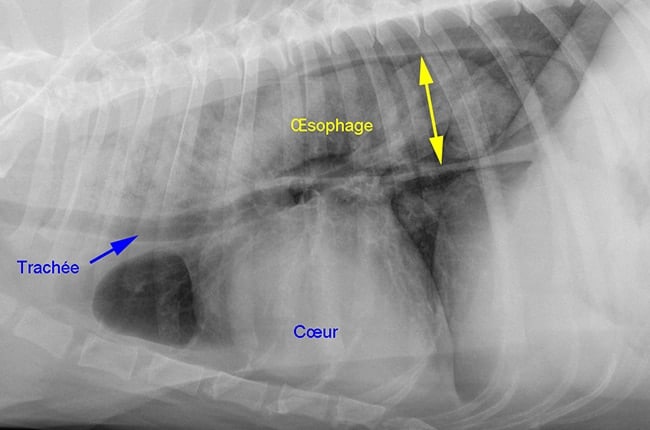

Certaines formes focales n’entraînent qu’un mégaœsophage qui peut (ou pas) être présent dans la forme généralisée.

La radiographie thoracique permet de rechercher la présence éventuelle d’un thymome.